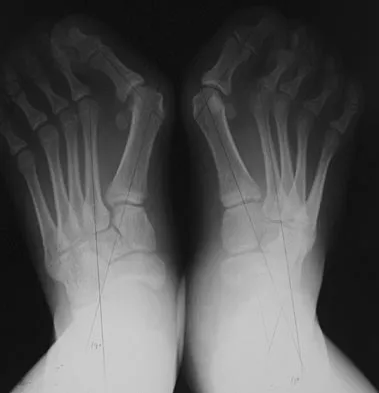

A 45-year-old woman has had intense pain in her foot for the last 3 days. She also reports a mild fever and difficulty with shoe wear. Examination reveals a swollen, slightly erythematous warm foot with tenderness at the great toe metatarsophalangeal joint and pain with passive motion of the joint. An AP radiograph is shown in Figure 13. Which of the following will best aid in determining a definitive diagnosis?

Explanation

The patient has gouty arthropathy of the first metatarsophalangeal joint. This definitive diagnosis is achieved with aspiration of the joint and polarized light microscopy that shows needle-shaped negatively birefringent monosodium urate crystals. Differential diagnoses of infectious arthritis and pseudogout are also definitively made through joint aspiration. Although rheumatoid arthritis is a possibility, a serum rheumatoid factor is not always diagnostic and a patient with rheumatoid arthritis may have concomitant gouty arthritis. The radiographic findings are not typical of diabetes mellitus or of a patient with Charcot arthropathy. Wise CM, Agudelo CA: Diagnosis and management of complicated gout. Bull Rheum Dis 1998;47:2-5.